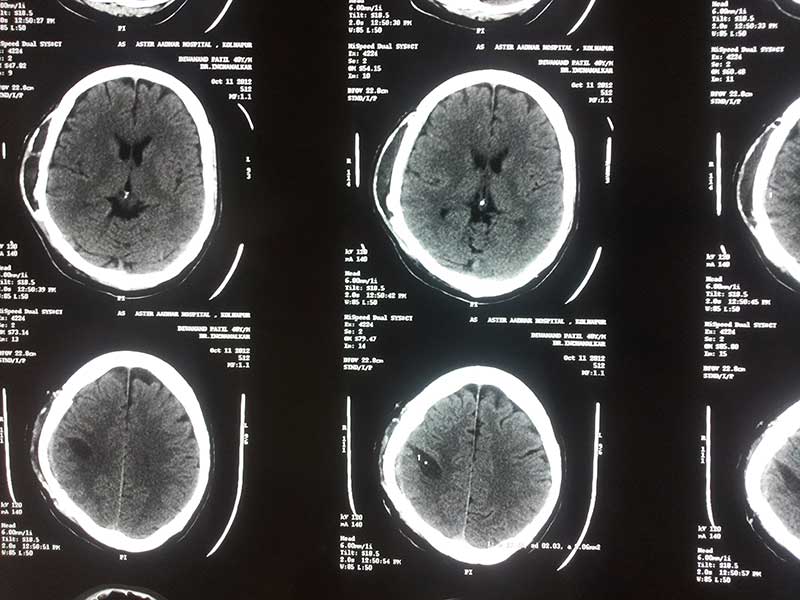

Post Op CT of Cavernoma